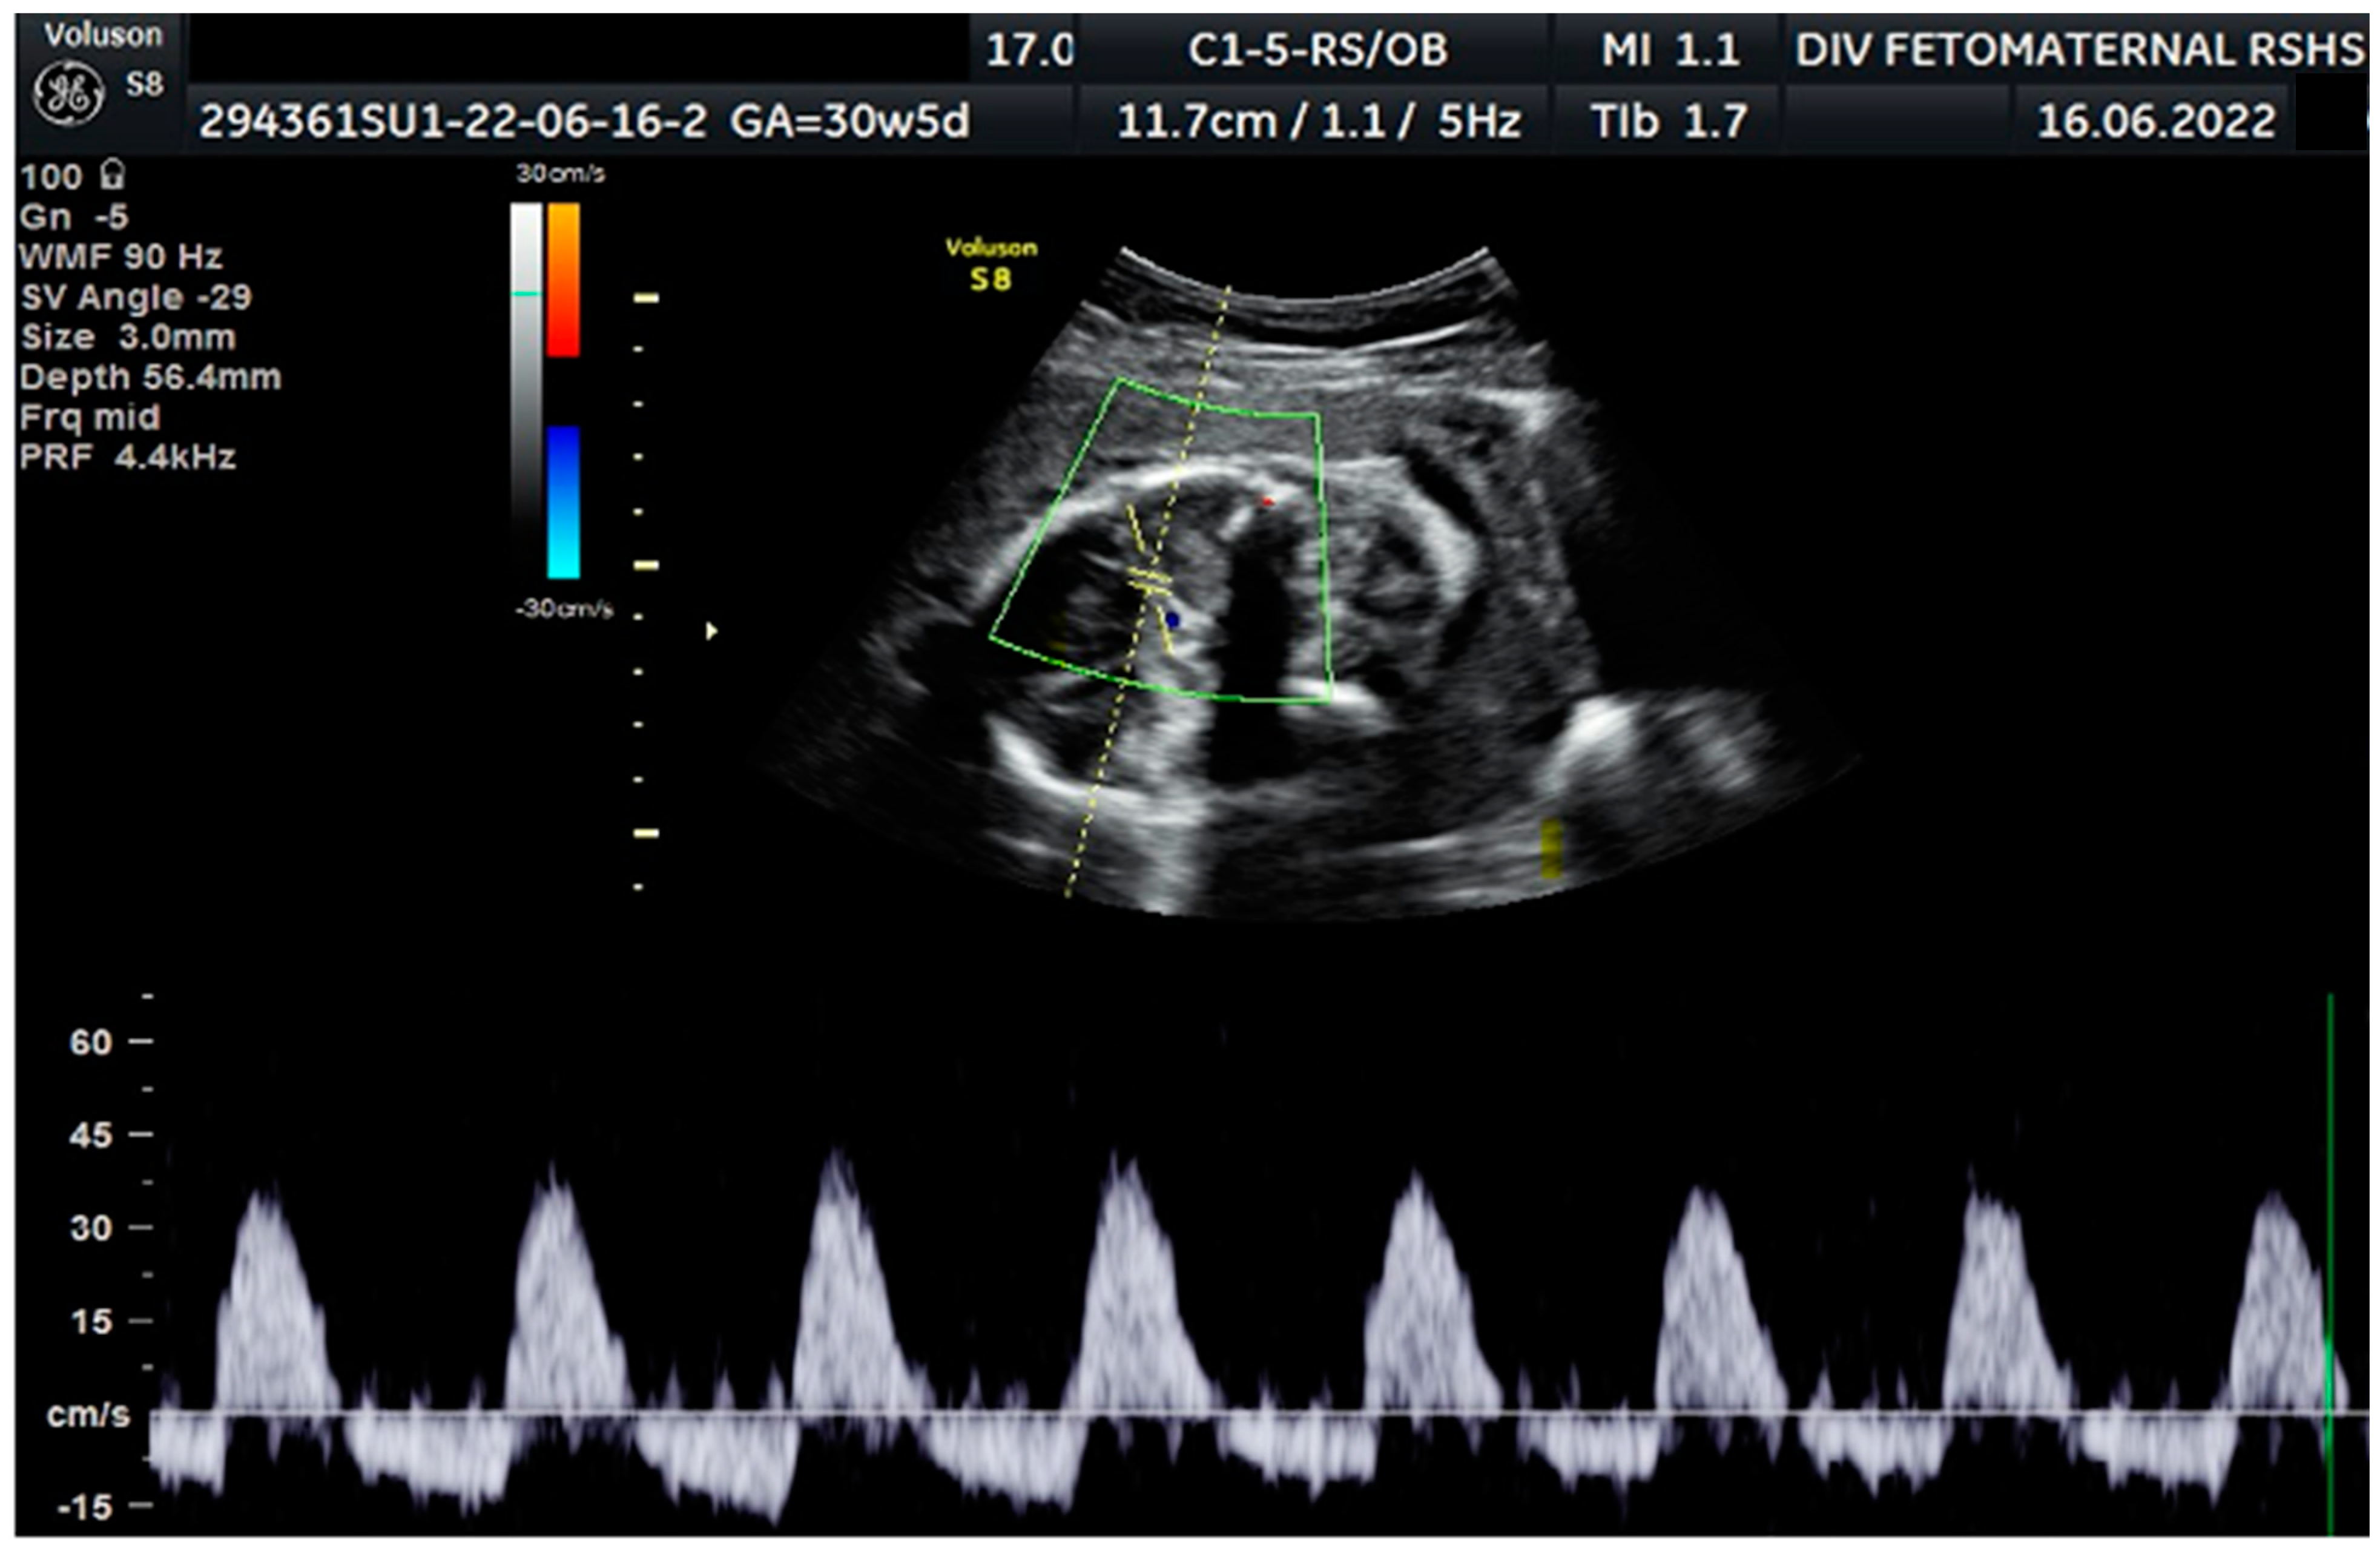

Figure 3. Notching on right and left uterine artery Doppler.

Color Doppler examination of the MCA revealed a peak systolic velocity of 42.33 cm/s, which is 1.045 times the median (the normal range is 40.5 cm/s for this gestational age), with persistent reversed end diastolic flow (Figure 2). The umbilical artery pulsatility index (PI) was 0.99, and RI was 0.63, with an S/D ratio of 2.71. There was notching on the right uterine artery, with a PI of 2.11. Notching was also found on the left uterine artery, with a PI of 1.58 (Figure 3). Laboratory results were within a normal range.

The Doppler examination also revealed a notching of the right and left uterine arteries, which is a marker of spiral artery remodeling failure, causing early-onset severe preeclampsia [11,12]. In this case, inadequate early prevention worsened the patient’s condition, leading to severe preeclampsia. The pregnancy did not present with hydrocephalus, cerebral hemorrhage, or mechanical compression of the fetal head. Another anatomical abnormality cannot be assessed intrauterine, nor seen after delivery. We did not perform a postnatal examination to exclude any internal neonatal anatomy abnormalities.